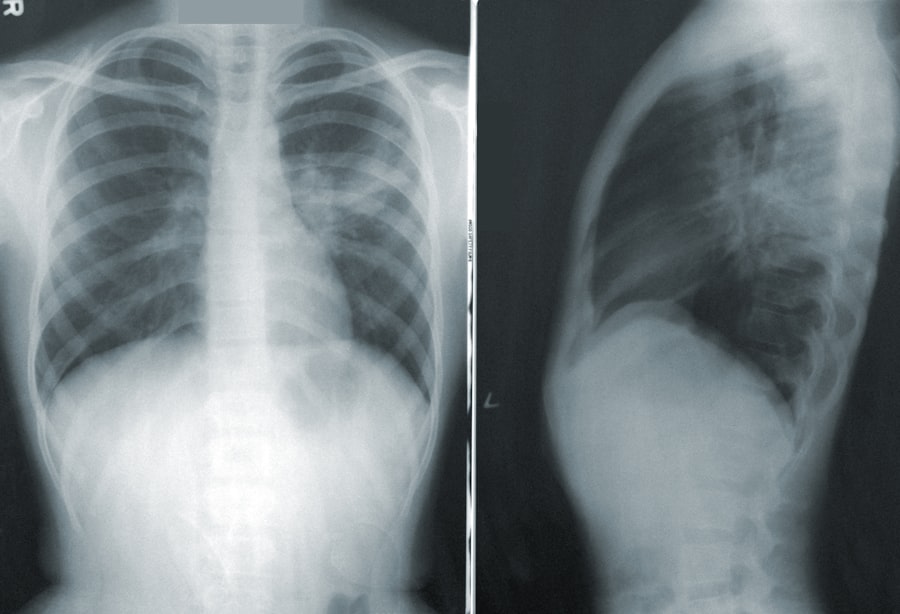

The connection between physical activity and mental well-being

The Mental Health Benefits of Exercise

Research has shown that even moderate exercise can lead to significant improvements in symptoms of anxiety and depression. Physical activity serves as a natural stress-reliever, providing an outlet for pent-up emotions while simultaneously boosting self-esteem.

The key to reaping the mental health benefits of physical activity is consistency rather than intensity. Even small amounts of movement can contribute significantly to mental health improvements. By finding physical activities that bring joy, individuals can make exercise a sustainable and enjoyable part of their routine.